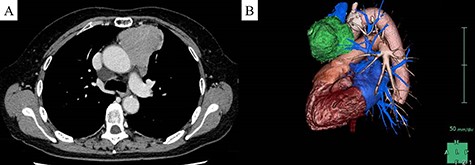

A 70-year-old woman with no symptoms was referred to our hospital because of an abnormal chest roentgenogram. Contrast-enhanced chest computed tomography showed a 62-mm anterior mediastinal tumor. On the basis of the results of 18F-fluorodeoxyglucose positron emission tomography, we suspected a thymic malignant tumor invading the pericardium and left phrenic nerve (Fig. 1). Surgery was indicated.

Preoperative image of the tumor. (A) Chest computed tomography revealed a 62-mm anterior mediastinal tumor. (B) Left lateral three-dimensional view of the tumor (green) indicated that the tumor appeared to invade the left phrenic nerve.